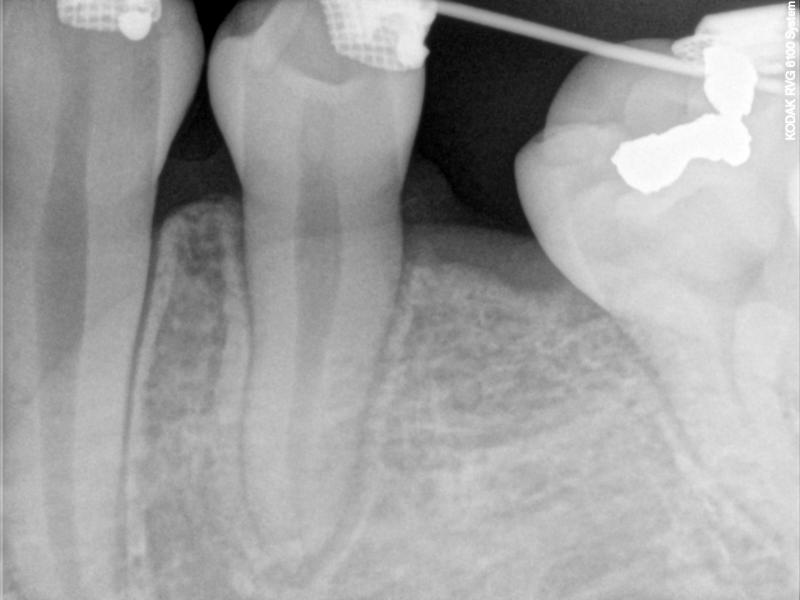

Fig. 2. The LLE is ankylosed.

© Copyright 2007-2014, Vu Orthodontics. All rights reserved.